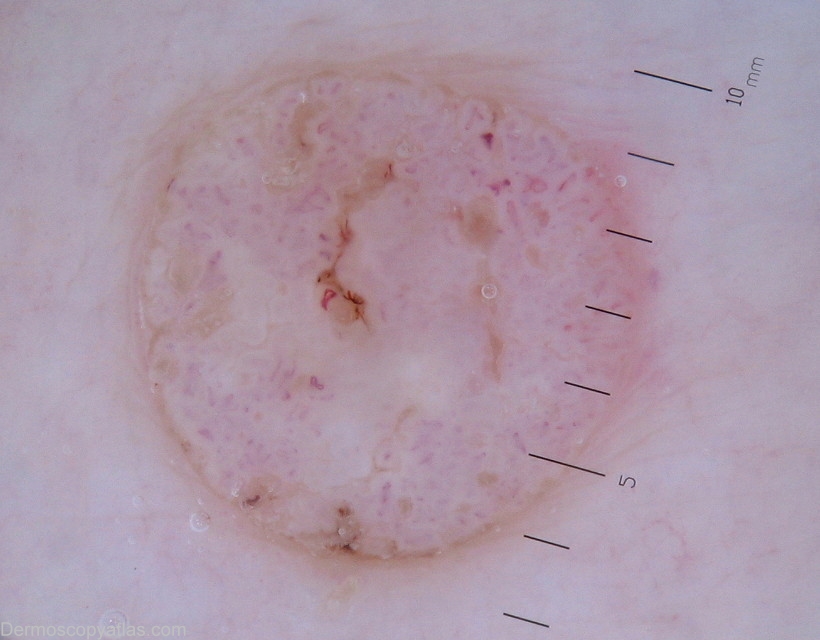

Image Number #2985 (Inkspot lentigene)

Site: Back

Diagnosis: Inkspot lentigene

Description: Dermoscopy -Right scapula area.Bizzare,black pigment network.

History of multiple non melanoma skin cancers.

Images of seborrheic keratosis was also illustrated along with inkspot(reticulated) lentigo.